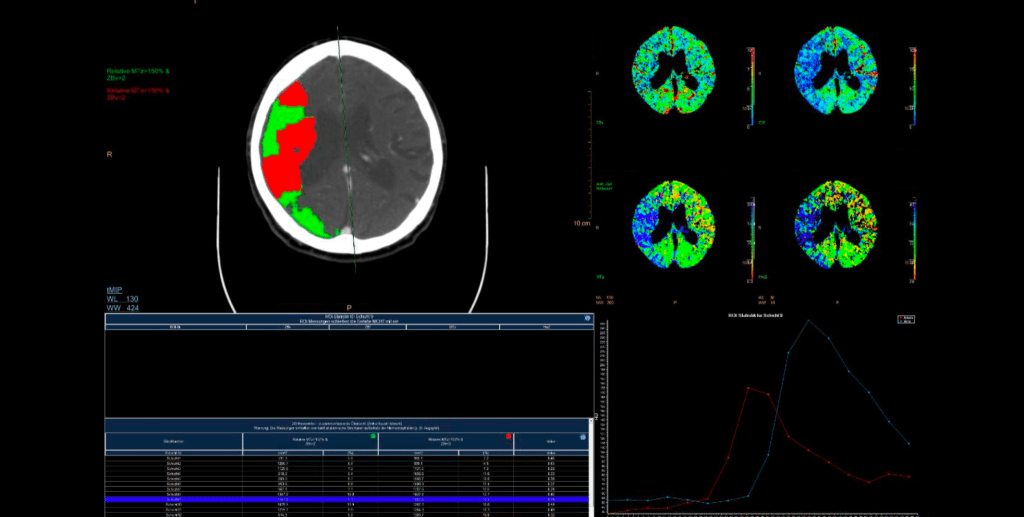

Typischerweise werden 40 ml Röntgen-Kontrastmittel mit relativ hoher Infusionsgeschwindigkeit (5 ml/s) infundiert. Dann wird durch repetitive CT-Messungen das An- und Abfluten des Kontrastmittels im Kopf gemessen, was über den Anstieg der Hounsfield Unit-Werte ja sogar quantifiziert werden kann. Dies macht man in den Arterien, den Venen und im Parenchym. Es entstehen bei den üblichen Protokollen ca. 30 CT-Aufnahmen hintereinander, welche alle 2 Sekunden angefertigt werden, so dass eine CT-Perfusionsmessung in der Regel ziemlich genau eine Minute dauert. Es gibt allerdings auch andere Protokolle und bei einer schlechten Pumpfunktion des Herzens ist das (so zeigt es auch die klinische Erfahrung) auch gar nicht so selten zu kurz. 30 CT-Aufnahmen hintereinander verursachen eine nicht unerhebliche Strahlenbelastung, auch wenn die Dosis pro CT-Messung schon reduziert wird (was man auch an der Bildqualität der CT-Perfusionsmessungs-Bilder sehen kann). Es entstehen dann zwei Messparameter (und das sind auch die entscheidenden, die anderen beiden kann man für die meisten Fälle erst einmal in den Skat drücken). Das sind die mittlere Transitzeit oder mean transit time oder MTT und das ist das zerebrale Blutvolumen oder cerebral blood volume oder CBV. Die MTT beschreibt die Zeit, die das Kontrastmittel zum An- und Abfluten im Hirngewebe braucht und ist am Ende eine Korrelation aus der Messkurve aus der Arterie und des Hirngewebe selber. Die CBV ist so ein schöner area under the curve-Messwert und vergleicht KM-Aufnahme im Hirnparenchym (unter der Kurve des An- und Abflutens) mit dem An- und Abfluten in den Venen (und hier auch als Fläche unter der Kurve). Die Idee ist dann, dass die CBV angibt, wo überhaupt noch Kontrastmittel hinkommt (eben nicht in den Infarktkern) und die MTT, wo das Kontrastmittel langsamer an- und abflutet, nämlich im Risikogewebe. Dazu kommt, dass im Risikogewebe durch die Weitstellung aller Kollateralgefäße das CBV meistens normal bis erhöht ist. Die beiden anderen – eher nicht so entscheidenden – Parameter sind dann noch die Halbwertszeit oder time to peak oder TTP, was einfach die halbe MTT bis zum Scheitelpunkt ist und der zerebrale Blutfluss oder CBF, was der Quotient aus CBV und MTT ist. Dies bedeutet, dass man – nach der Idee hinter der CT-Perfusionsbildgebung – dann in der CBV den Infarktkern und in der MTT die Penumbra sehen würde und kleiner Infarktkern und große Penumbra dann unsere Mismatch-Analogie darstellen würde.

Für den anspruchsvollen Connaisseur sei noch erwähnt, dass die TTP in erster Linie im CT-Protokoll auftaucht, weil sie in der MRT-Perfusionsbildgebung relativ viel benutzt wird und dass das ganze (die MRT-Perfusion noch mehr, das werden die Freunde der CT-Perfusion auch nicht müde zu betonen), daran krankt, dass es keine allgemein akzeptierten und standardisierten Messwert-Grenzen gibt, da das Ergebnis der Perfusionsbilder relativ stark vom Gerät, seinen Einstellungen, der Software, dem Hersteller, dem Patienten und seiner kardinalen Pumpfunktion usw. abhängt. Das führt dann oft zu solchen Aussagen wie: “Aber hinten links ist es doch irgendwie ein bisschen blauer in der MTT“. Ganz grob konnte man sich darauf einigen, dass eine MTT von 4-6 Sekunden normal ist und dass eine Verdoppelung der MTT (und/oder der TTP) für eine signifikant schlechtere Perfusion spricht. Für den CBF gibt es sogar eine Dreiteilung: > 50 ml/100 g Hirngewebe ist normal, bei < 20 ml/100 g Hirngewebe liegt eine ischämische Situation vor und unter 10 ml/100 g Hirngewebe eine strukturelle Infarzierung. Beim CBV muss man wissen, dass im Kortex typischerweise mehr Blut ist als im Marklager (was auch irgendwie nicht verwundert), da geht man physiologischerweise von 5-6 ml/100 g Hirngewebe im Kortex und von 2-3 ml/100 g Hirngewebe im Marklager aus. Bei einem kortikalen CBV von weniger als 2 ml kann man einen Infarktkern annehmen. In der hinteren Strombahn, in der ja langsamere Flussgeschwindigkeiten vorherrschen, sind vor allem die MTT- und TTP-Werte deutlich länger.